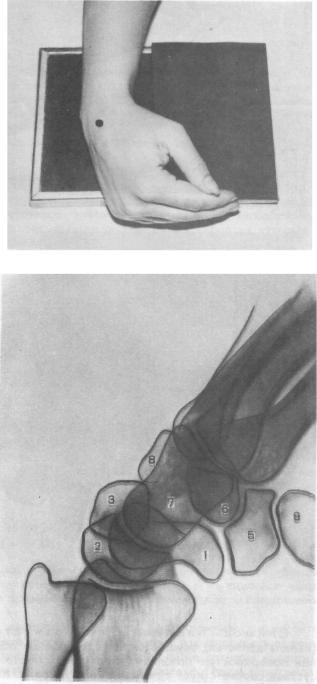

Подборка рентгеновских снимков лучезапястного сустава

Раздел: Объективный взгляд